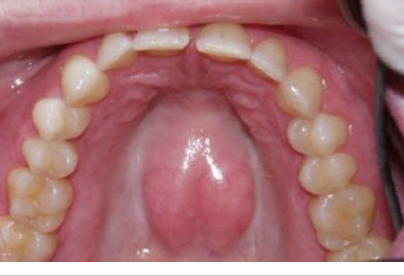

torus palatinus

usually in the midline